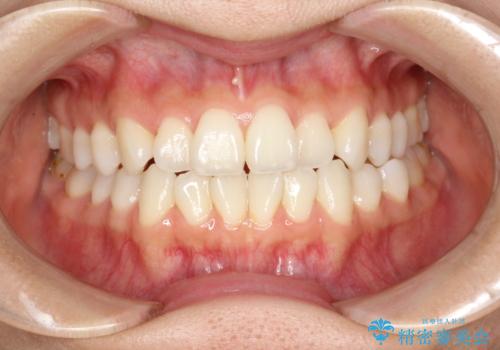

右上の前から2番目の歯が引っ込んで、下の前歯にはガタガタがありました。

上下の歯と歯の間を少量ずつ削りスペースを作り、インビザラインにて並べる計画としました。